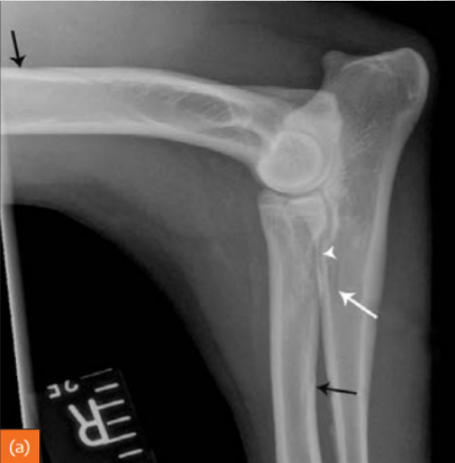

Describe Premature closure of growth plate.

e.g. distal ulna such as in image

results in growth discrepancy and may disrupt the function of the joint